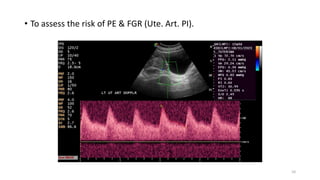

• To assess the risk of PE & FGR (Ute. Art. PI).